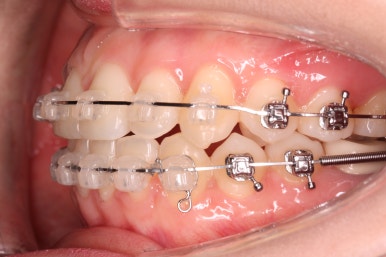

부산부정교합 키다리아저씨치과에 처음 내원하셨을 때의 입안 모습입니다.

위아래 앞니가 삐뚤고 특히 왼쪽 위 송곳니는 밖으로 두드러져 덧니 양상입니다. 윗니는 덧니쪽으로 쏠려 있어서 치열의 중앙이 맞지 않습니다.

전반적인 삐뚤어진 양, 돌출의 느낌, 골격의 비율 등을 고려했을 때 발치 없이 치료를 하기로 했습니다.